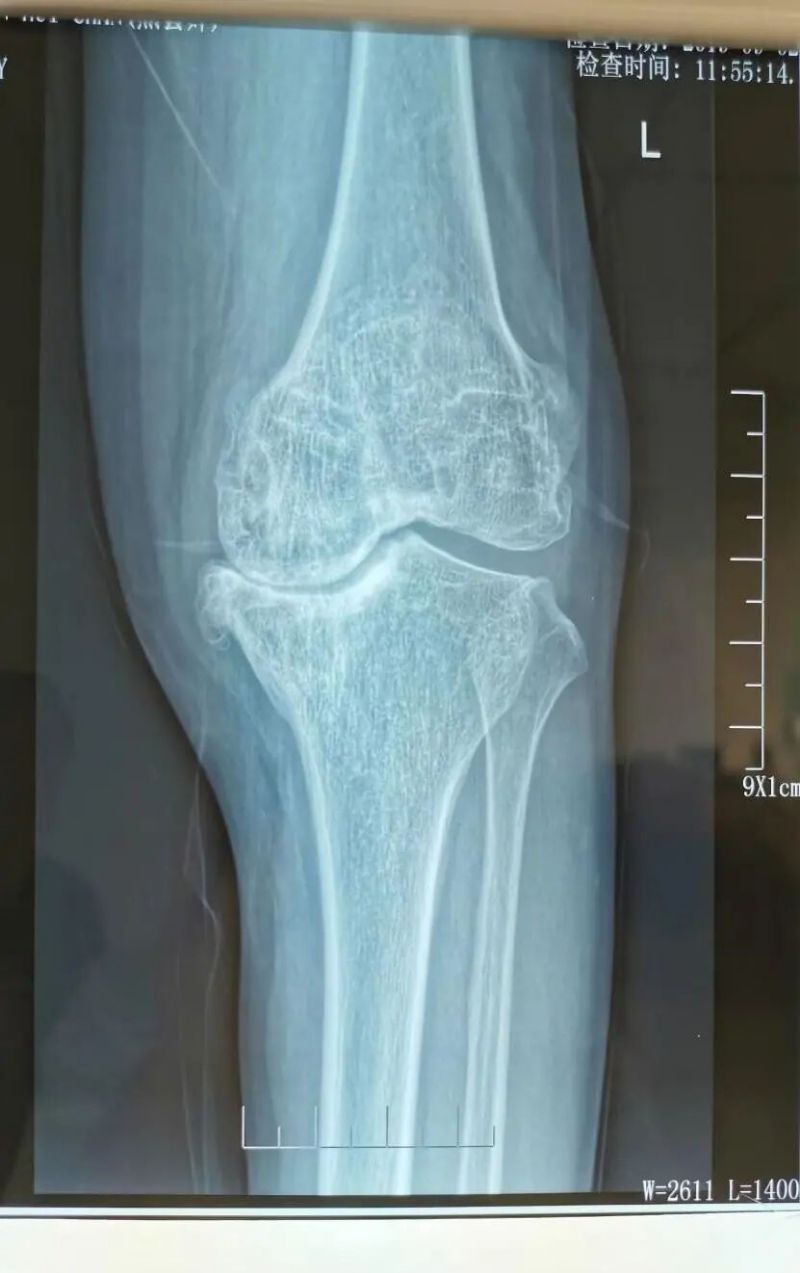

影像學(xué)檢查是診斷的重要手段。X線檢查就像給關(guān)節(jié)拍了一張“照片”,能夠清晰地顯示關(guān)節(jié)間隙變窄、骨質(zhì)增生、軟骨下骨硬化等典型表現(xiàn)。而MRI檢查則更像是一部“高清攝像機(jī)”,能更清晰地觀察關(guān)節(jié)軟骨、半月板、滑膜等軟組織的病變情況,為醫(yī)生提供更準(zhǔn)確的診斷依據(jù)。

第三階梯:修復(fù)性治療。當(dāng)保守治療無(wú)法滿意控制病情時(shí),可考慮微創(chuàng)或矯形手術(shù)。①關(guān)節(jié)鏡清理術(shù):通過(guò)微創(chuàng)切口,清除關(guān)節(jié)內(nèi)的炎性滑膜、破碎的軟骨和游離體。②截骨術(shù):通過(guò)矯正下肢力線,將身體重量從磨損嚴(yán)重的一側(cè)轉(zhuǎn)移到相對(duì)健康的一側(cè)。

第四階梯:終極治療。當(dāng)關(guān)節(jié)軟骨嚴(yán)重磨損,出現(xiàn)持續(xù)劇痛、嚴(yán)重畸形和功能障礙時(shí),人工關(guān)節(jié)置換術(shù)是最終,也是最有效的解決方案,能極有效地解除疼痛、改善功能,顯著提升生活質(zhì)量。